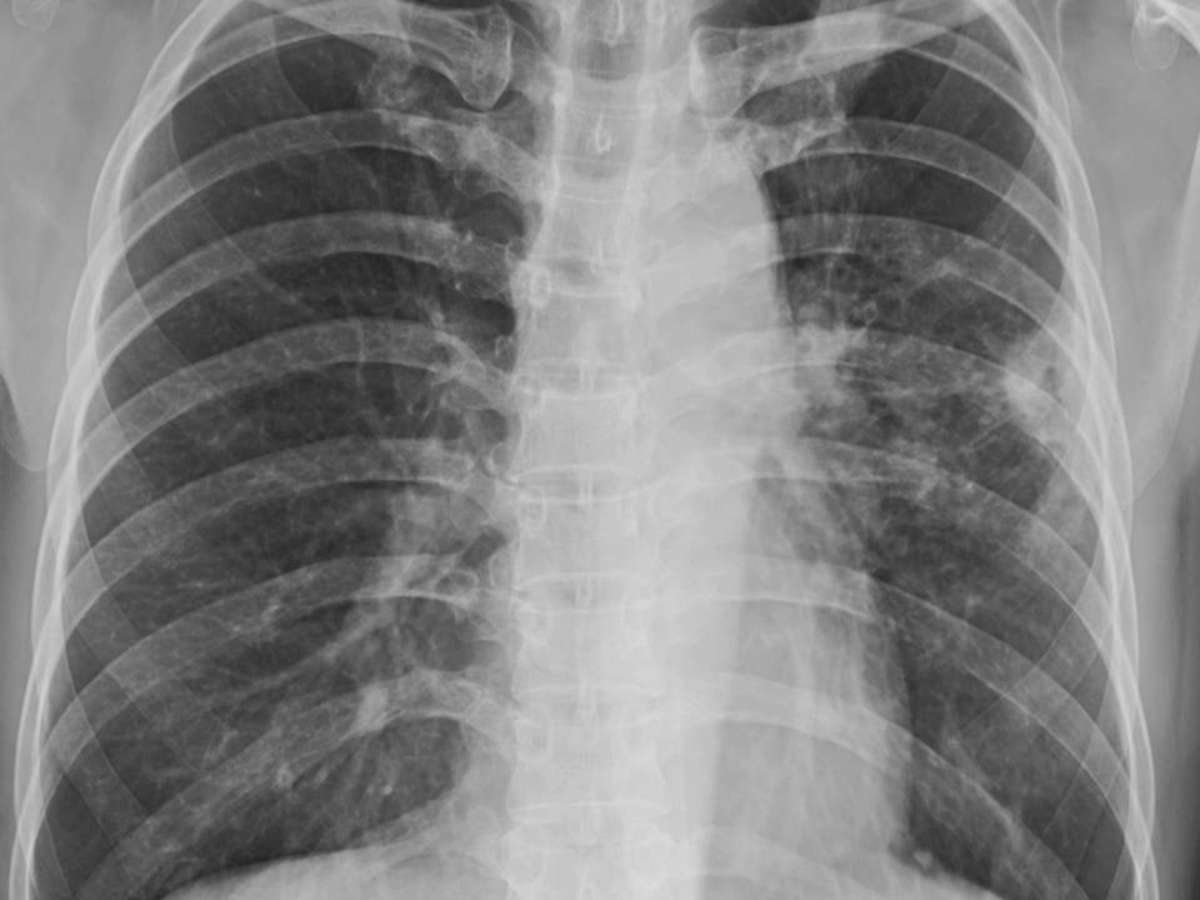

câncer – depositphotos.com / Chinnapong